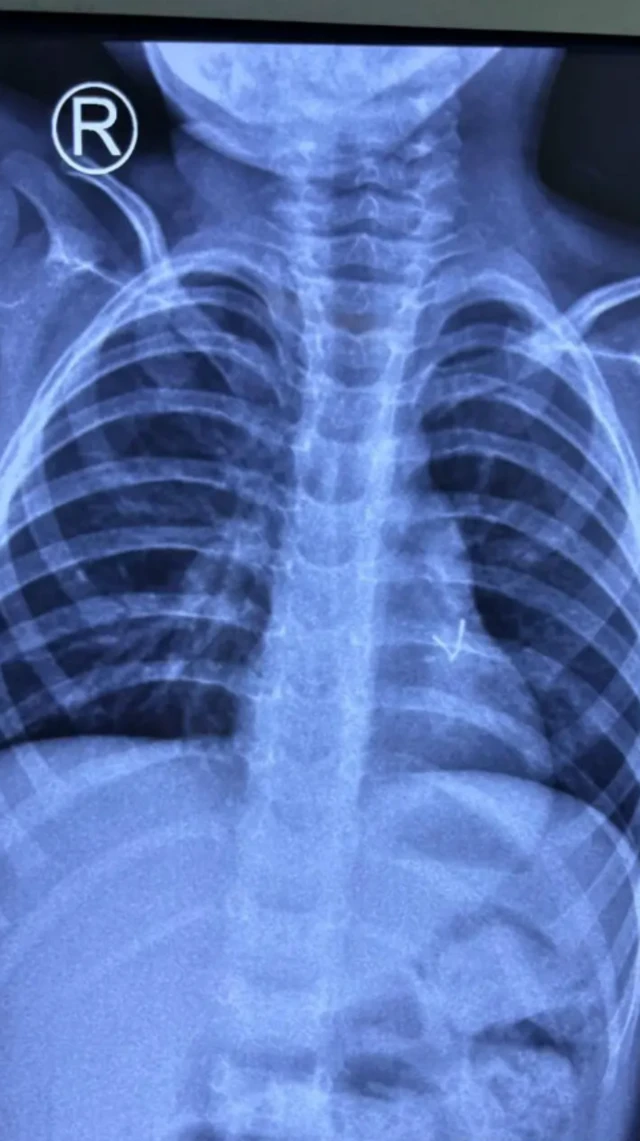

ਚੰਗੀ ਦੇਖਭਾਲ ਦੇ ਬਾਵਜੂਦ ਵੀ ਉਸ ਦੇ ਲੱਛਣ ਬਣੇ ਰਹੇ। ਫਿਰ ਉਸ ਦੀ ਹੋਰ ਜਾਂਚ ਕੀਤੀ ਗਈ, ਜਿਸ ਵਿੱਚ ਸੀਟੀ ਸਕੈਨ ਵੀ ਸ਼ਾਮਲ ਸੀ, ਜਿਸ ਵਿੱਚ ਉਸ ਦੇ ਖੱਬੇ ਬ੍ਰੌਨਚਸ ਵਿੱਚ ਡੂੰਘਾਈ ਵਿੱਚ ਧਾਤੂ ਦਾ ਇੱਕ ਟੁਕੜਾ ਨਜ਼ਰ ਆਇਆ।

ਡਾਕਟਰ ਰਾਜਪੂਤ ਕਹਿੰਦੇ ਹਨ, "ਜੇਕਰ ਇਹ ਵਸਤੂ ਬੱਚੇ ਦੀ ਭੋਜਨ ਨਲ਼ੀ ਵਿੱਚ ਦਾਖਲ ਹੋ ਗਈ ਹੈ, ਤਾਂ ਬੱਚਾ ਰੋਵੇਗਾ ਅਤੇ ਕੁਝ ਸਮੇਂ ਬਾਅਦ ਉਹ ਸ਼ਾਂਤ ਹੋ ਜਾਵੇਗਾ। ਇਸ ਤੋਂ ਬਾਅਦ ਤੁਹਾਨੂੰ ਡਾਕਟਰ ਕੋਲ ਜਾਣਾ ਚਾਹੀਦਾ ਹੈ ਅਤੇ ਛਾਤੀ ਅਤੇ ਪੇਟ ਦਾ ਐਕਸ-ਰੇ ਕਰਵਾਉਣਾ ਚਾਹੀਦਾ ਹੈ ਅਤੇ ਉਨ੍ਹਾਂ ਦੇ ਸੁਝਾਅ ਅਨੁਸਾਰ ਇਲਾਜ ਕਰਨਾ ਚਾਹੀਦਾ ਹੈ।''